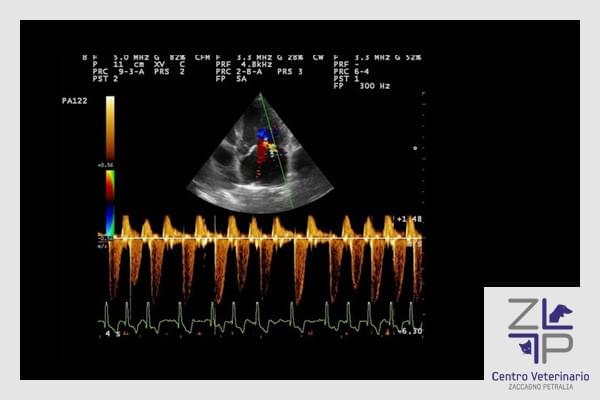

Ecografia ed Ecocardiografia ufficiale

La nostra struttura offre un servizio ecografia color -doppler, mediante strumenti all'avanguardia, fornisce informazioni necessarie al raggiungimento della diagnosi e per la valutazione dei successivi follow up. Inoltre eseguiamo esami ecografici specialistici per la valutazione delle patologie cardiache nel cane e nel gatto, (esame ecocardiografico ed elettrocardiogramma ufficiale).